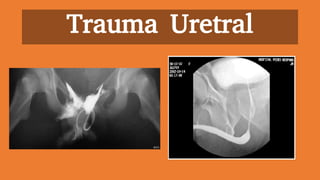

Trauma Uretral

Trauma de Uretra

Diagnostico:

1. Evaluacion clinica:

- Sangre en el meato

- Sangre en el introito vaginal

- Hematuria

- Dolor al orinar

- Hematoma o hinchazon

- Prostata de ubicacion alta

Exploracion radiologica:

1. Uretrografia retrograda

Tratamiento:

1. Lesiones ureterales anteriores:

- Cistostomia suprapubico

2. Lesiones ureterales posteriores:

- Uretroplastia